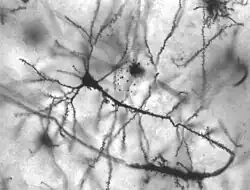

| Neurons in person with epilepsy, 40x magnified | |